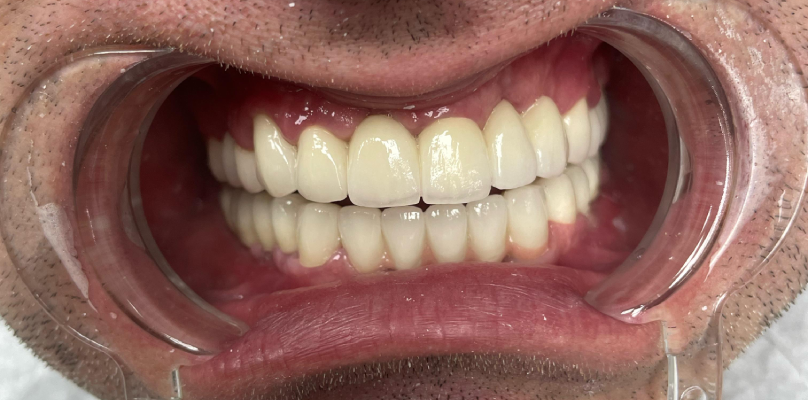

Entretiens

Une fois le traitement terminé, vous pourrez visionner nos entretiens avec nos patients et entendre leurs expériences. Ces entretiens, qui racontent comment leur qualité de vie s’est améliorée en peu de temps et la valeur ajoutée du traitement implantaire à leur santé, seront une source d’inspiration pour nos autres patients.

Nous considérons toujours la satisfaction de nos patients comme une priorité. Nous vous accompagnons à chaque étape du traitement par implants buccaux complets. Nous sommes heureux de vous aider à faire le bon choix pour votre santé et votre sourire.